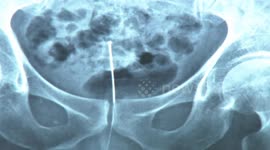

A doctor removed part of a broken metal tube from an elderly man's urethra in southern China.

In the video, shot in the city of Xinyu in Jiangxi Province on January 8, a 3-centimetre-long broken metal tube is seen stuck in an elderly man named Hu's urethra via an X-ray film.

The doctor named Yuan Jian used a cystoscope to take the broken metal tube out of Hu's body.

According to reports, Hu inserted a metal tube into his urethra to help with urination but a part of it broke inside his body.